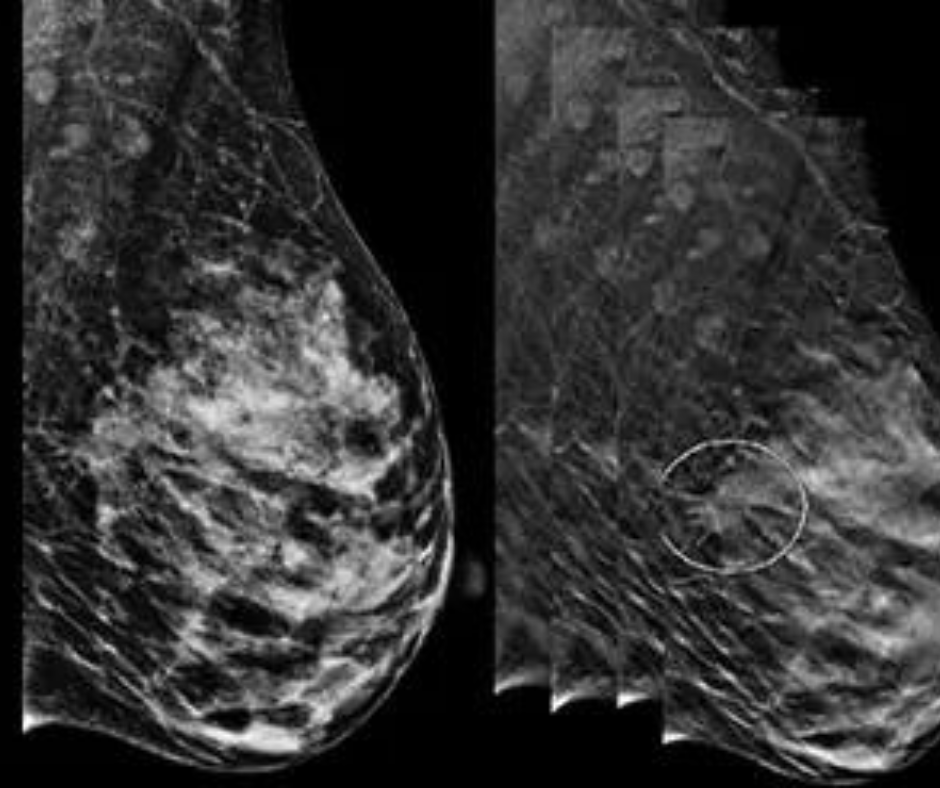

Diffusion-weighted imaging may be useful as a safe and effective screening tool to supplement mammography in women with dense breast tissues.

The impact of digital breast tomosynthesis on screening performance and screen-detected cancers appears to generalize beyond trials and academic centers to the community setting.

Digital breast tomosynthesis offers benefits over mammography, but it is enough to change screening?